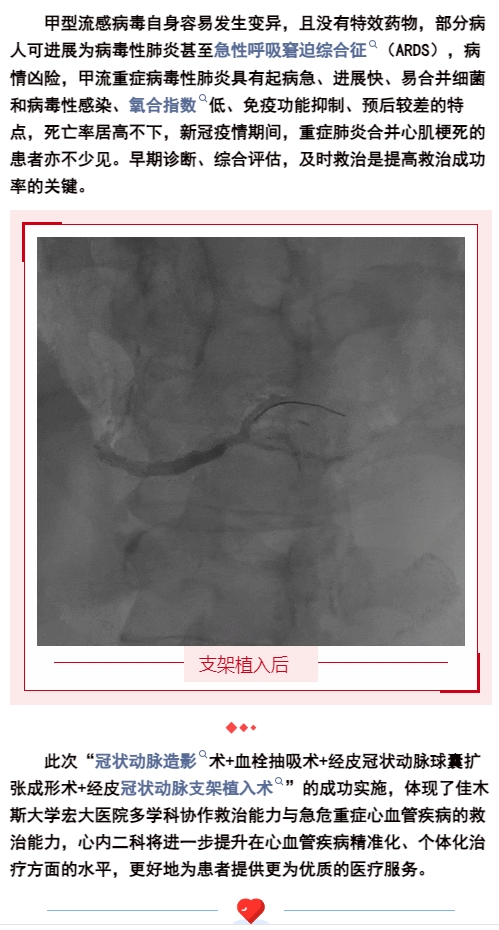

生死時(shí)速,為“心”護(hù)航,為患者打開(kāi)生命之門(mén)!【佳木斯大學(xué)宏大醫(yī)院】